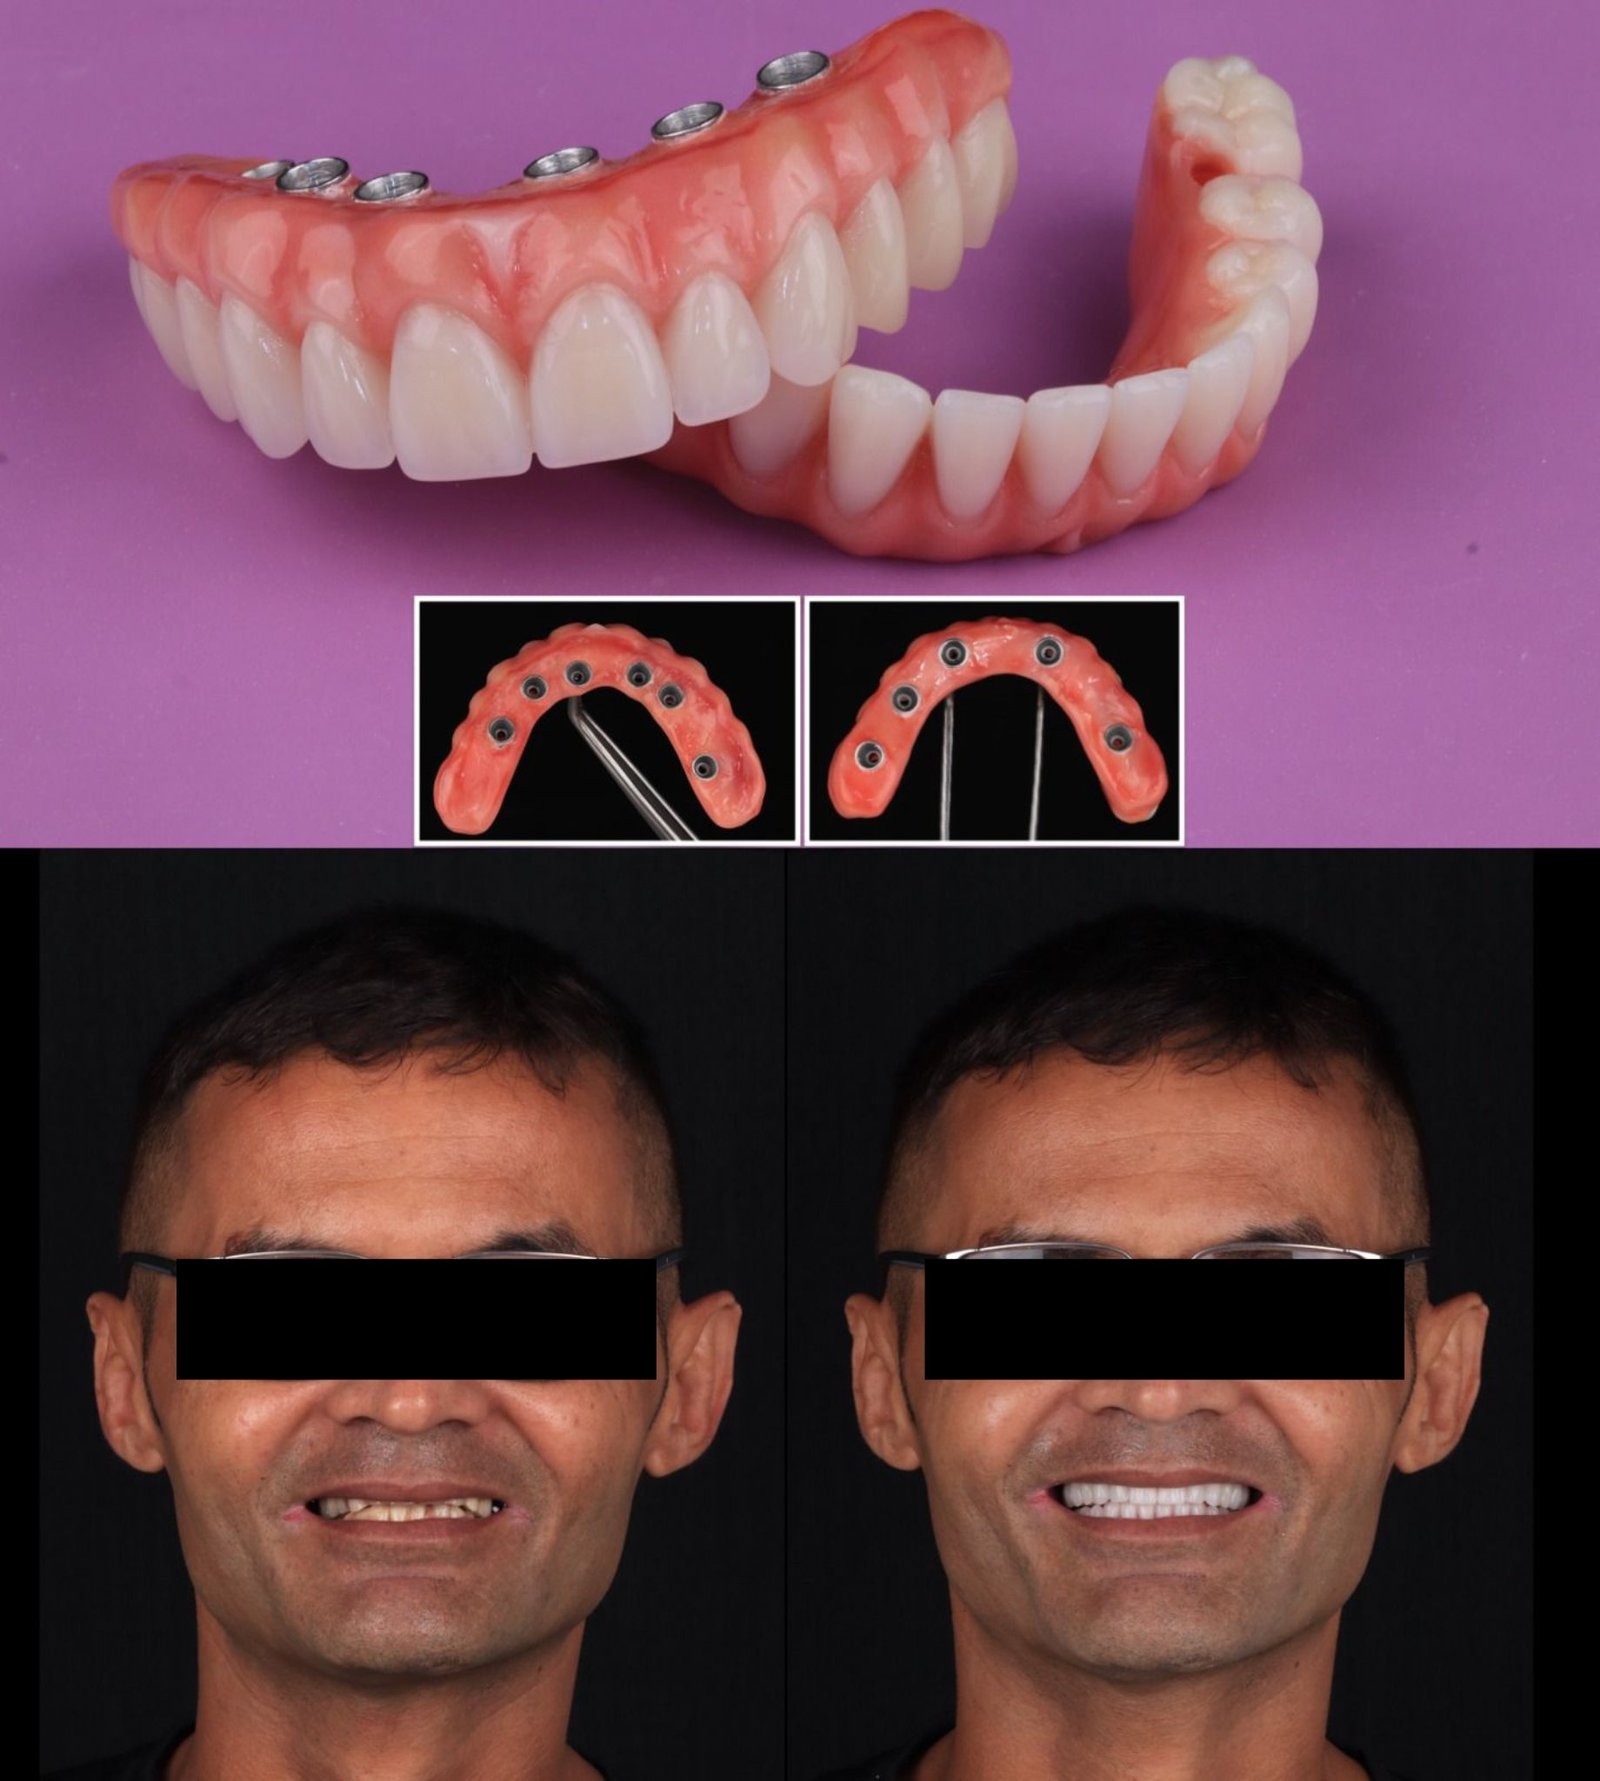

Antes & depois — arraste para comparar

Casos reais tratados na clínica. Deslize o divisor para ver a transformação.

Resultados da clínica

Especializada em estética dental, com foco em facetas em porcelana, implantes e clareamento, ela atende em clínica própria na Praia da Costa, em Vila Velha.